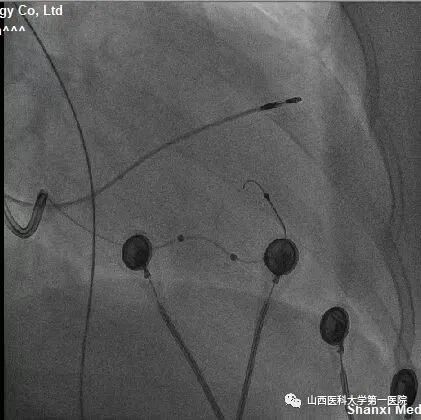

该患者为老年女性,主因反复间断胸闷10余年,加重1周入院。完善相关检查后提示:窦性心律,QRS波宽度187ms、完全左束支传导阻滞形态;心脏彩超显示:左室射血分数:25%,  左室舒末内径:72mm,符合ESC2021CRT指南I类适应证。术中,冠状窦静脉造影发现左室电极靶静脉(左室侧静脉)迂曲,双导丝导丝(Runthrough NS和Pilot50)均无法通过,采用逆向导丝技术,从后静脉逆向进入迂曲的静脉分支及侧支,成功进入左室侧静脉。